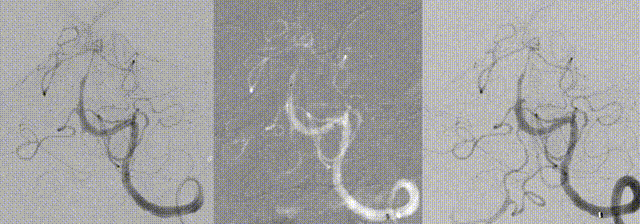

The stent expanded and apposed well, with good in-stent flow and improved visualization of distal branches.

15-minute follow-up angiography showed stable in-stent flow in the basilar artery

Postoperative CTA confirmed patency of the stented segment